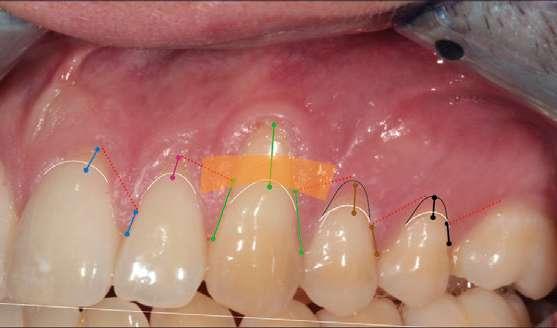

En la exploración clínica observamos recesiones gingivales múltiples en maxilar superior combinado con erosión de la encía y ligero desgaste cervical que borra la línea amelocementaria (Fig. 1). El sondaje periodontal en todos los dientes fue inferior o igual a 3 mm y no se detectaron puntos de sangrado al sondaje. Los dientes 1.3 y 2.3 mostraron ≤ 1 mm de encía queratinizada apical a la recesión. Cabe también destacar la rotación del incisivo lateral superior derecho (1.2). El principal factor etiológico de sospecha en este caso fue el cepillado agresivo.

Después de un detallado análisis y valoración de las alternativas terapéuticas, se planificaron 2 procedimientos quirúrgicos mediante colgajos de avance coronal con acceso lateral y sin descargas para el tratamiento de las recesiones del maxilar superior (Fig. 2) (7-9).

A continuación procederemos a describir el paso a paso del tratamiento quirúrgico de las recesiones (Figs. 2 a 7). Ambos procedimientos quirúrgicos se realizaron bajo anestesia local y sedación consciente por vía endovenosa y con un tiempo de descanso para el paciente entre procedimientos de 1 mes y medio. En este caso, el eje de rotación fueron los caninos en ambos lados y todas las incisiones para-marginales oblicuas (líneas punteadas en rojo) se realizaron hacia estos dientes (Fig. 2).

Figura 1: Situación inicial. Obsérvese la recesión gingival profunda en 1.3 y 2.3, así como la erosión gingival y el borrado de la línea amelocementaria debido al cepillado agresivo.

Figura 2. Planificación quirúrgica.

Figura 4. Diseño de las incisiones y del colgajo. Nótese la creación de una “falsa recesión” en

colgajo al finalizar el avance coronal.

Figura 3. Situación clínica el día de la intervención quirúrgica.

Cada incisión oblicua debía permitir el correcto movimiento lateral y coronal de la punta de la papila quirúrgica hacia su papila anatómica correspondiente. Las incisiones para-marginales oblicuas debían conectar la parte más apical de la recesión con un punto final ubicado en la base de la papila de los dientes vecinos. La altura de este punto final se midió desde la punta de la papila y corresponde a la altura de la recesión + 1 mm. Adicionalmente, para permitir llevar a cabo un colgajo sin descargas, conseguir el suficiente avance coronal a nivel de 2.3, así como una buena adaptación del colgajo en premolares, se realizaron “falsas recesiones” (10) a nivel de 2.4 y 2.5 (Fig. 4). Finalmente, y de acuerdo con los estudios de Stefanini y colaboradores (9), se planificó aplicar el injerto de tejido conectivo (ITC) de manera sitio-específica en los dientes 1.3 y 2.3 debido a la presencia de una banda de encía queratinizada apical a la recesión ≤ 1 mm (Fig. 2 y 5).